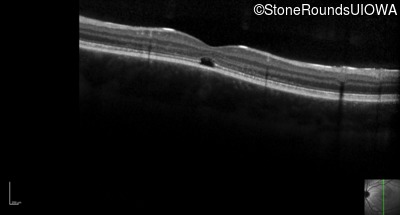

Optical Coherence Tomography - Left - 20/80 -1

Exemplar / OCT Stack

OCT Stack